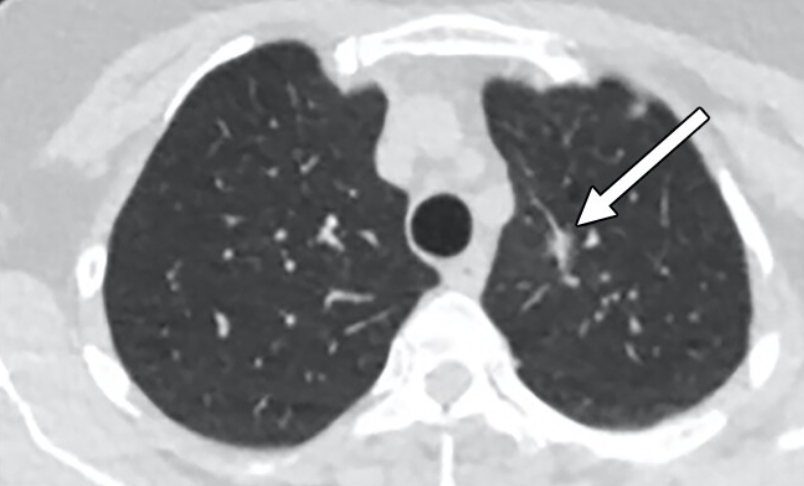

폐암은 초기에 특별한 증상이 거의 없어서 조기 발견이 어렵습니다. 흉부 엑스레이는 폐암을 찾아내는 첫 번째 단계로 사용돼요. 작은 혹이나 결절이 보이면 추가로 저선량 CT(방사선량이 적은 컴퓨터 단층촬영)를 진행하게 되죠.

하지만 엑스레이만으로 모든 폐암을 잡아내긴 어려워요. 종양이 아주 작거나 혈관 뒤쪽에 숨어 있으면 안 보일 수도 있습니다. 그래서 흡연력이 있거나 가족력이 있는 분들은 1년에 한 번 정도 저선량 CT를 병행하는 게 좋아요. 저희 아버지도 금연 후 매년 CT를 찍고 계신데, “한 번 찍으면 마음이 편하다” 하시더라고요. 그 말이 참 와닿았어요. 예방이 곧 안심이니까요.